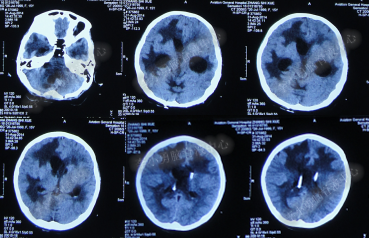

第3次手术右侧脑室外引流术后1个月时间内,脑积水仍没有得到控制,再给予腰大池引流,期间多次试图拔除右侧脑室外引流管(多次调高脑室外引流管的高度),但因患者意识变差,而无法拔除引流管,给予拔除腰大池引流,治疗期间曾多次查头部CT均示脑积水仍无改善(图-20、图-21、图-22、图-23)。

图-20:2014年7月24日头部CT

图-21:2014年7月29日头部CT

图-22:2014年8月4日头部CT

图-23:2014年8月15日头部CT